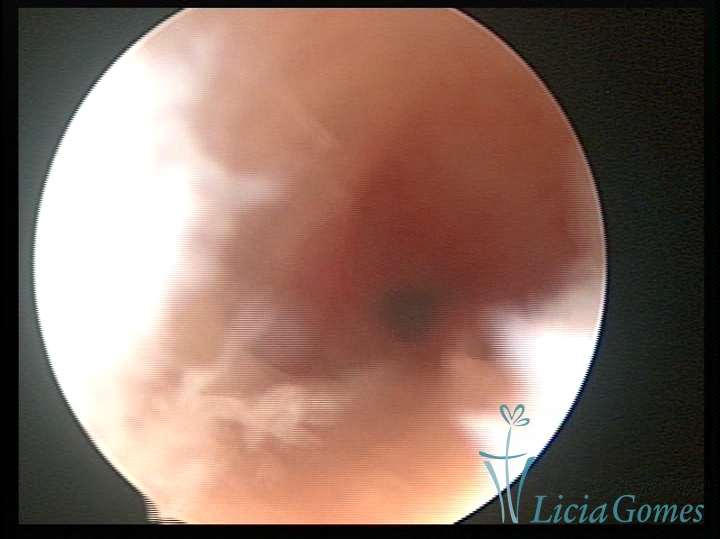

Bicornuate uterus

Malformation in which there is the lack of the flat portion of uterine fundus due to the lack of fusion on the proximal portion of paramesonephric ducts. The uterine fundus has two narrowed spaces in a divergent oblique angulation. It may be complete, from the fundus to the cervix; or partial, completely dividing the uterine cavity.

The tilted uterus which presents the most difficult hysteroscopic diagnosis occurs when there is only a small indentation of the uterine fundus.